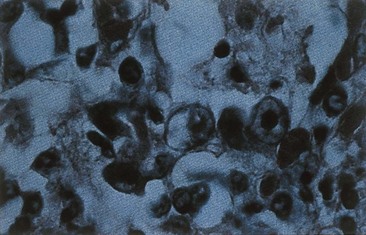

The histologic hallmark of adenovirus infection is a dense, central intranuclear inclusion (that consists of viral DNA and protein) within an infected epithelial cell (Figure 50-3). These inclusions may resemble those seen in cells infected with cytomegalovirus, but adenovirus does not cause cellular enlargement (cytomegaly). Mononuclear cell infiltrates and epithelial cell necrosis are seen at the site of infection.

image

Figure 50-3 Histologic appearance of adenovirus-infected cells. Inefficient assembly of virions yields dark basophilic nuclear inclusion bodies containing DNA, proteins, and capsids.